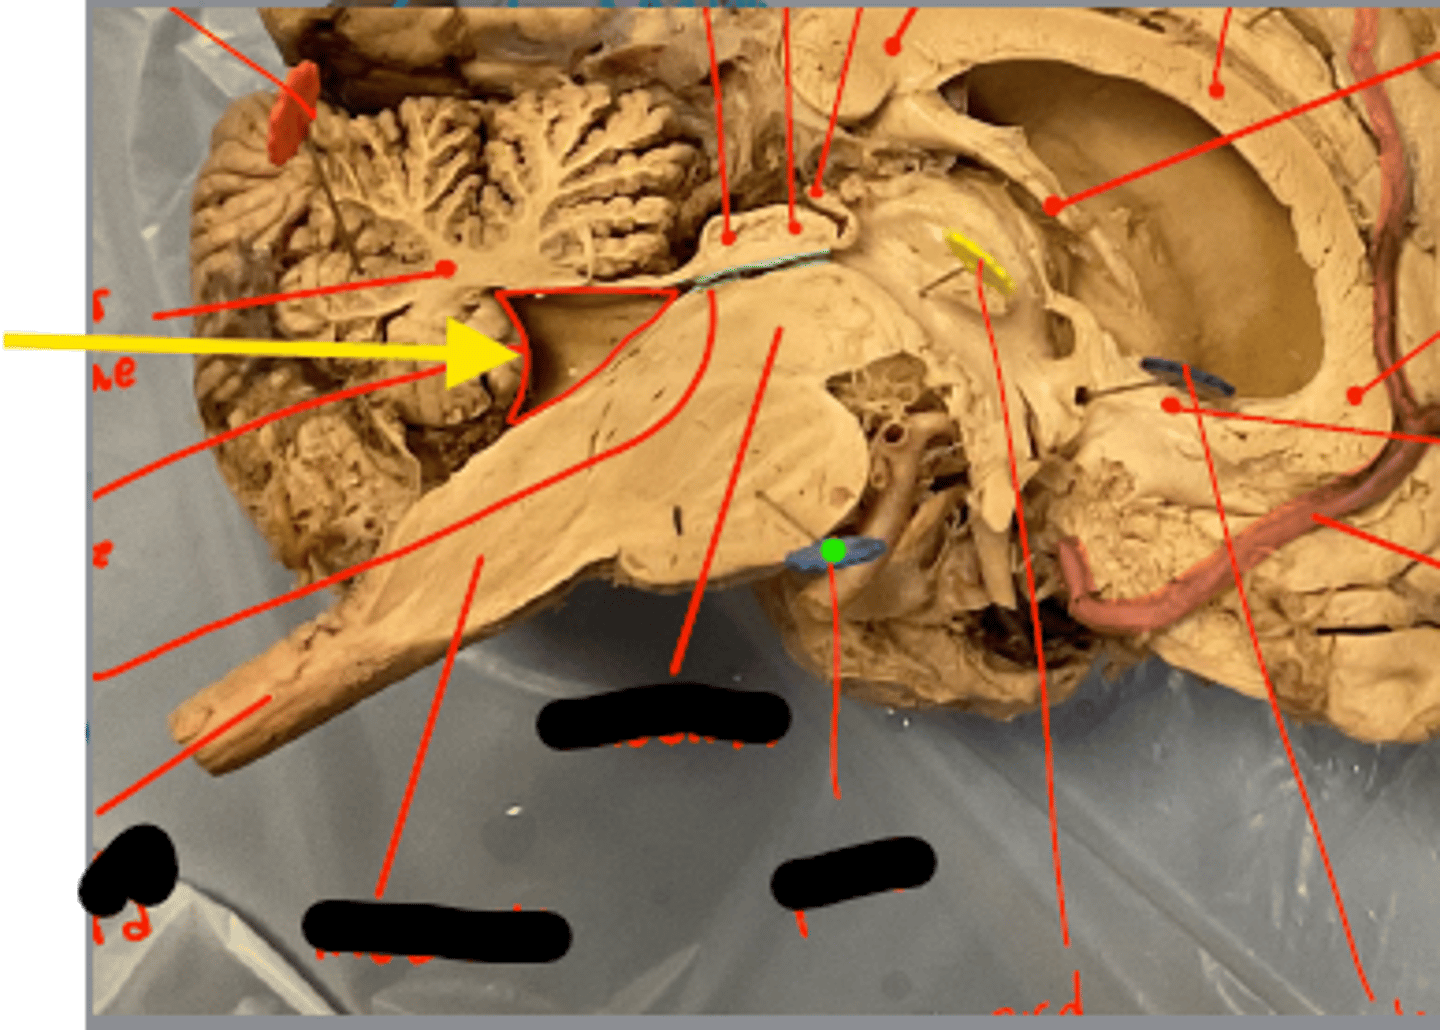

What space is the yellow arrow pointing to?

What part is the yellow arrow pointing to?

what space is the yellow arrows pointing to?

Name the structure the yellow dot is on.